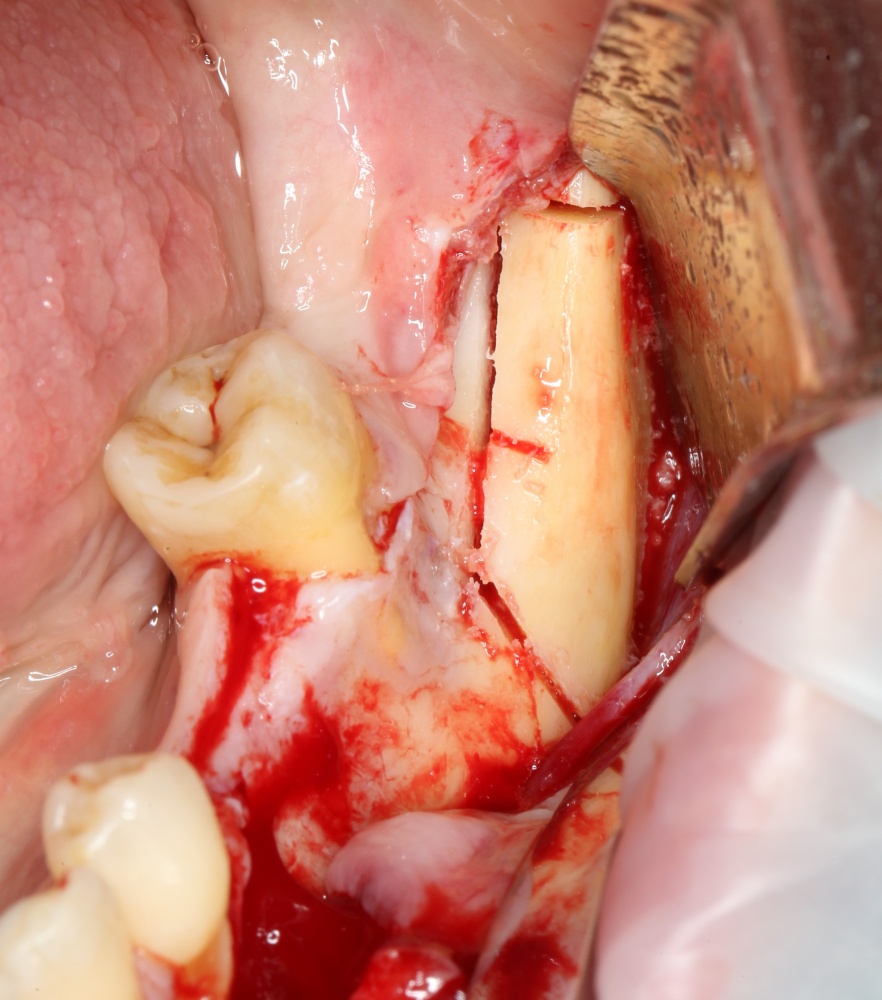

Переставляя винты и пришлифовывая аутокостный фрагмент, можно добиться более-менее точного соответствия принимающему ложу:

A09A5457 (2) A09A5458 (2)

Теперь можно готовить лунки под импланты:

A09A5459 (2)

В данном случае я планирую установить импланты Nobel Replace Conical Connection:

A09A5461 (2) A09A5462 (2)

Операция почти закончена. Обратите внимание, на два момента:

1. Блок явно больше, чем нужно. Это связано с тем, что в процессе интеграции происходит атрофия графтов (причем, абсолютно любых), и мы должны закладывать этот уровень атрофии при планировании объемов костной пластики. В среднем, плюс 30% к тому, что нам нужно.

2. Между блоком и принимающим ложем есть пустое пространство. Поэтому область операции необходимо изолировать барьерной мембраной от быстро растущих мягких тканей. Я использую Geistlich BioGide 25×25 mm: